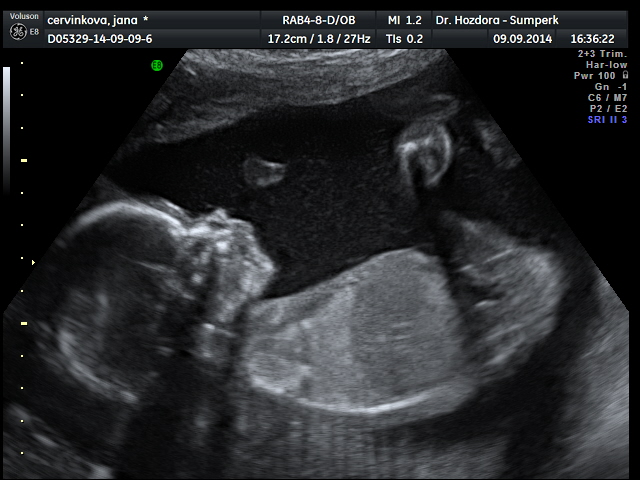

Děvčata,po dnešním ultrazvuku zvyšuju skore holčiček na 13:12. Bude to Marie Jana

Jsem tak happy.